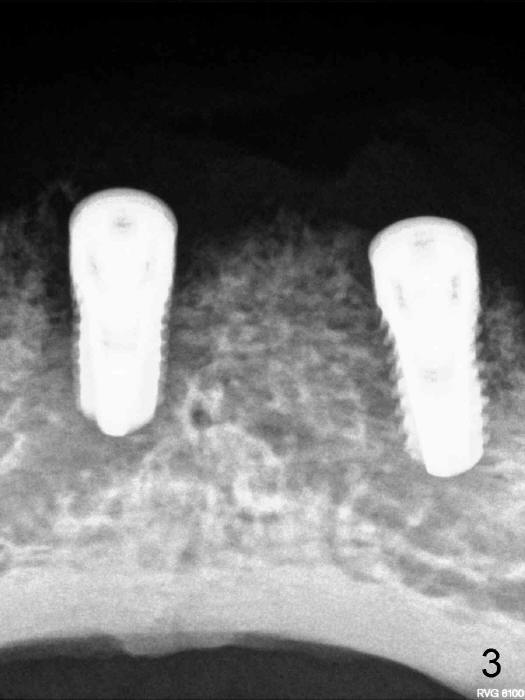

The patient, whom we discussed about, lower two implants supported overdenture, was back for implant check near two months.  The fistula seems getting better .I did one pa x ray(Fig.4) and irrigated with H2O2, same as last time. what else I can do for this case, observation or replacing implant?

Bob: Thanks for nice presentation with attachment.  You asked a good question.  It appears that the radiolucency does not decrease as compared to 1 month follow up.  Even though the clinical sign improves, the right implant will be fibrointegrated at the best.  If I were you, I would open up soon.  If bone is healthy around the implant, remove granulation tissue if present.  If it looks bad, remove the implant and place a larger one if walls are intact.  Pack bone graft and place a collagen membrane.  I would place an extra implant as a bonus for the patient and punishment on myself so that I would never forget.  Premedicate the patient.  Make an incision so that you may extend it later if necessary for the bonus.

As you are aware, I am not satisfied with X-ray taken by your assistants.  Three PAs for this case do not show implant threads.  It suggests that X-ray is not taken parallel.  Your implant may unexpectedly heal, but the X-ray may not.  You have to do something.  Find X-ray book and read the first few chapters, particularly how to take X-ray: parallelism.  Thanks.  2nd you have to write down insertion torque # when finishing a case.  In case if fails, you may figure out why.